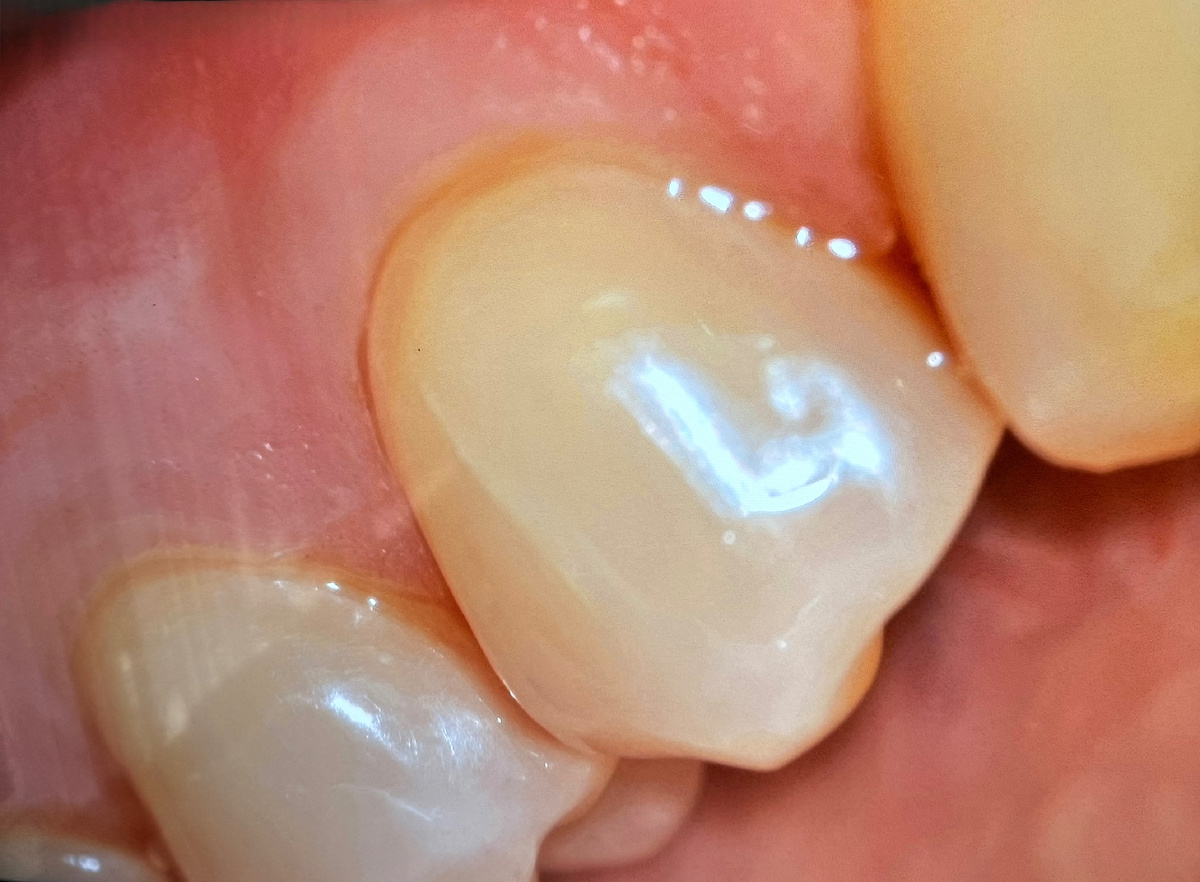

"Начинающийся клин на 34 зубе. Едва видно. Пациенты такое не замечают. Да что там пациенты - врачи не все видят! Микротрещина на передней стенке, свежая выемка. Не часто на такой ранней стадии удаётся засечь проблему" - и высылает фотографию:

Начинающийся клиновидный дефект

Клиновидный дефект - это V-образная выемка в пришеечной области зуба. Там, где коронка переходит в корень. Выглядит как будто кто-то топориком вырубил кусочек в стволе дерева.

Начинается с микротрещинки, потом углубляется и вот это уже маленькая бороздка. Потом выемка. В финале, если не исправить "фундамент" - глубокий клин, который может доходить до самого нерва и, даже, приводить к перелому зуба.